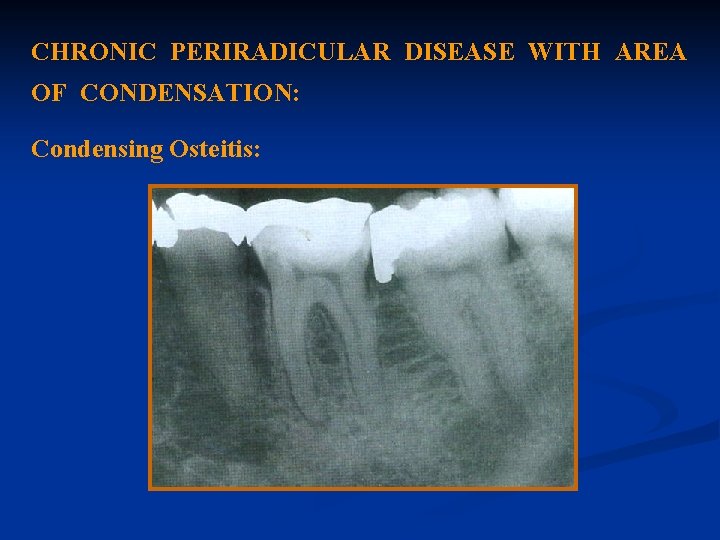

CHRONIC PERIRADICULAR DISEASE WITH AREA OF CONDENSATION: Condensing Osteitis:

Diagnosis: The diagnosis is made from radiographs. Condensing osteitis appears in radiographs as a localized area of radiopacity surrounding the affected root.